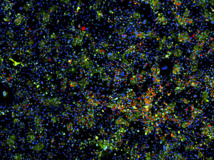

En la imagen, las manchas verdes identifican a las células del hígado, y las rojas a las células que se están dividiendo activamente. Imagen: Shan et. Al. Nature Chemical Biology. Fuente: MIT.